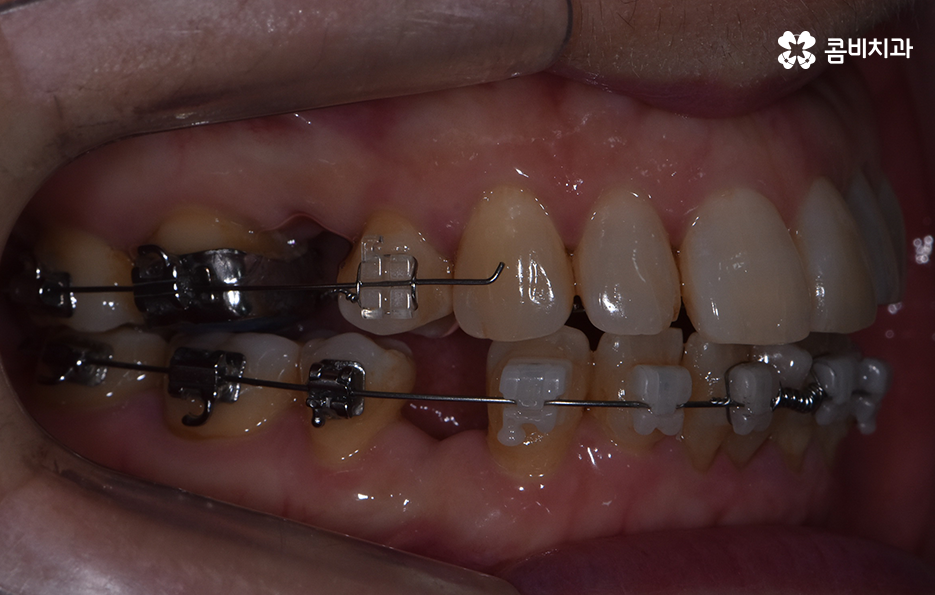

오늘 보시는 교정 사례의 경우를 보시면 아랫니의 틀어짐도 크지만 측면 사진으로 보시면 치열로 인해 돌출입에 영향을 준다는 사실도 알 수 있어요. 즉 치열과 함께 돌출입도 함께 고치고 싶어하기 때문에 치열도 재배열 하지만 치아 안쪽으로 넣어서 입술라인과 얼굴형으로 볼 때도 돌출입도 치료하는 치료 계획을 세웠기 때문에 작은 어금니 발치를 통한 치아의 이동 공간을 확보한 사례로 볼 수 있어요

콤비교정은 윗니는 설측으로 진행하고 아랫니는 순측으로 교정기를 착용하기 때문에 웃을 때 주로 보이는 앞니는 교정기 착용이 티가 안난다는 점에서 크게 웃지 않는다면 교정기 착용이 거의 티가 안나는 수준으로 교정을 진행할 수 있어요